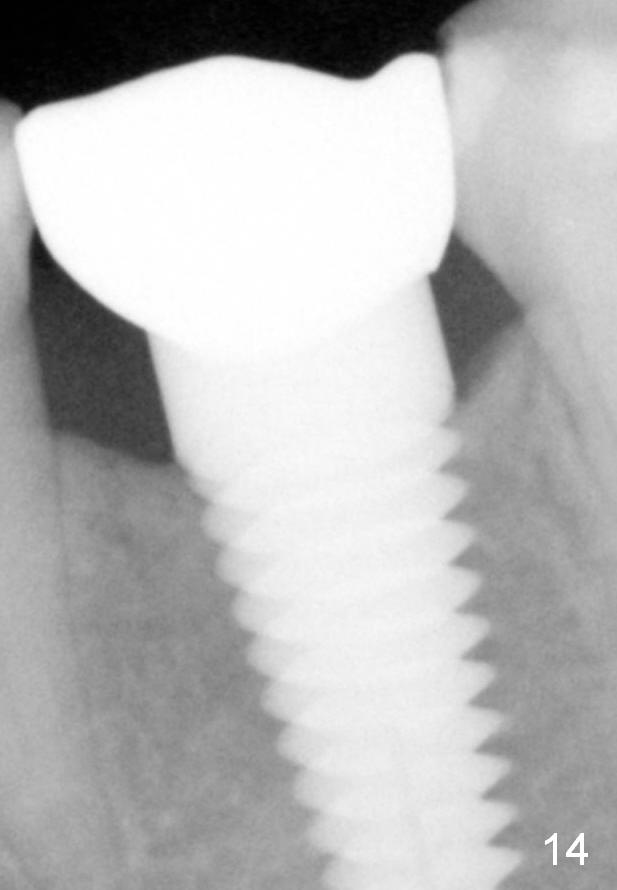

Eleven months post bonding (17 months postop), there is cortical bone formation at the mesial and distal crests (Fig.14). It remains the same 1 year 10 months post bonding (Fig.15). There is no bone loss 3 years 5 months post cementation (Fig.16). In fact the crestal cortical bone thickens.